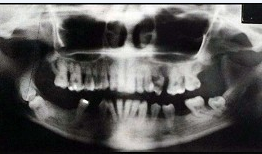

关于快速进展性牙周炎,哪项正确()

A、发病年龄青春期至25岁之间

B、病损好发于第一恒磨牙和上下前牙

C、有严重及快速的骨破坏,然后破坏过程自然停止或显著减慢

D、所有患者都有中性粒细胞及单核细胞的功能缺陷

E、本病极少伴有全身症状

正确答案:

C